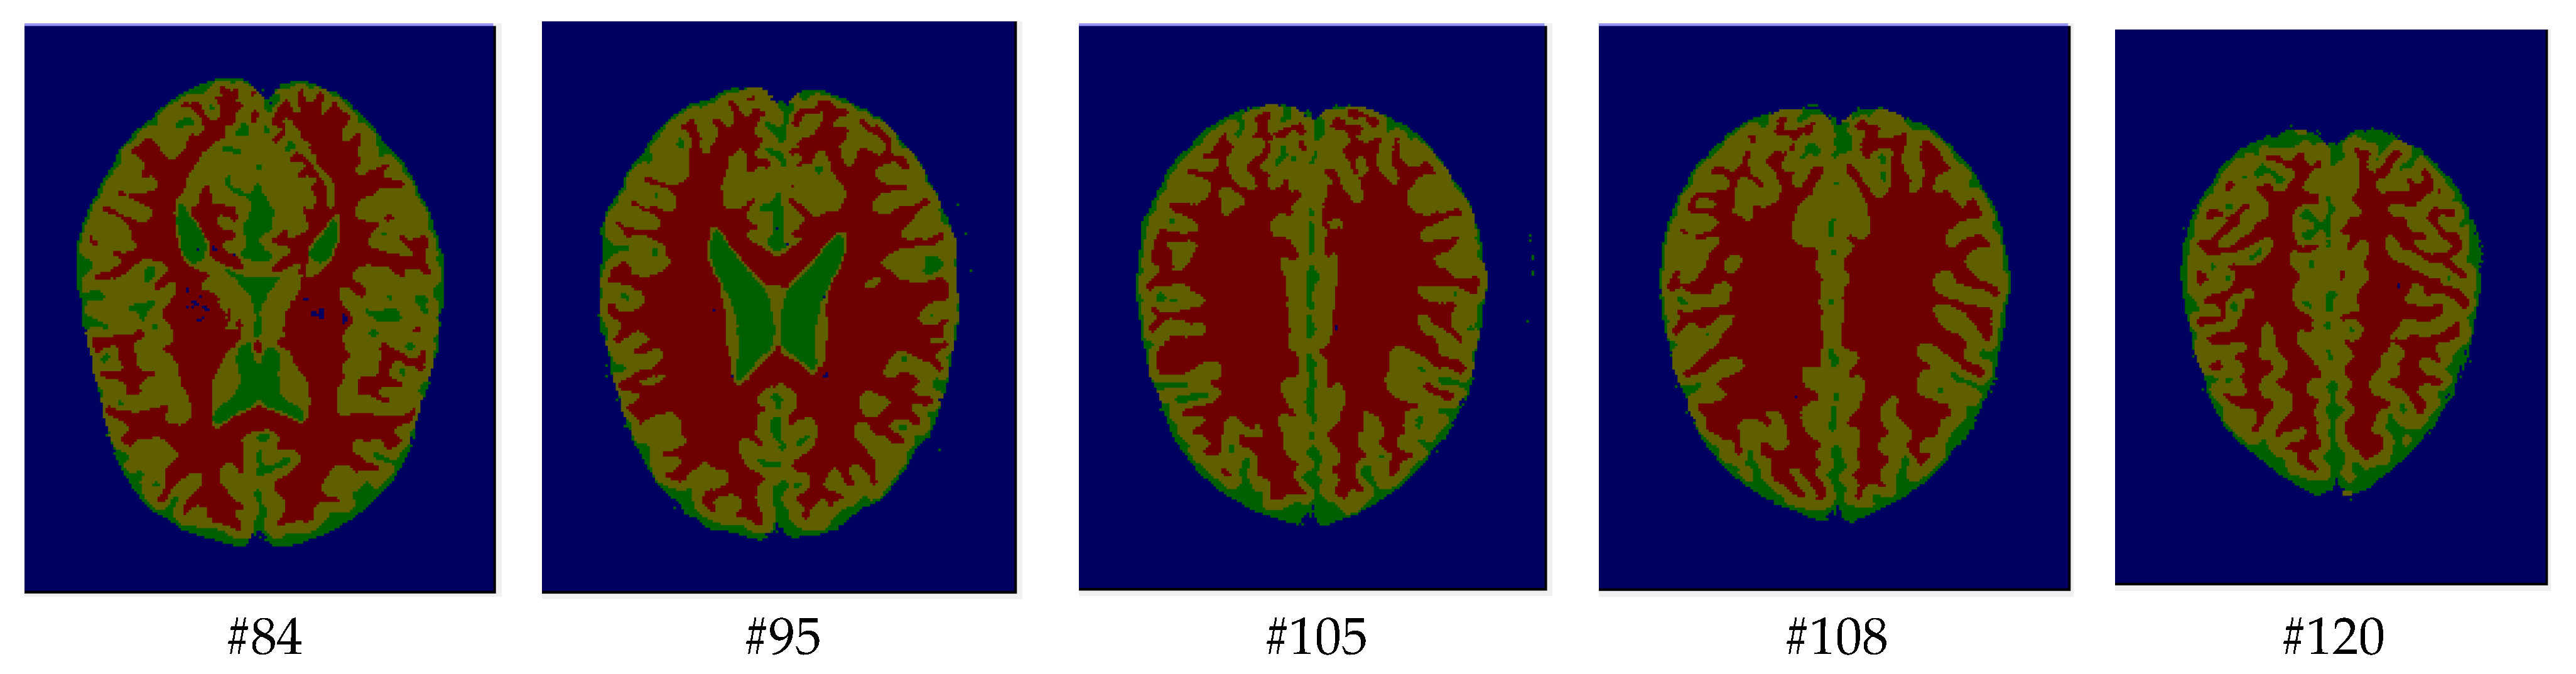

As mentioned before, the images of the first five datasets in Table 3 were used to evaluate the performance of the HMRF-WOA. Figure 1, Figure 2, Figure 3, Figure 4 and Figure 5 show some slices of a T1-weighted image (slices: 84, 95, 105, 108, 120). These brain images correspond to the slices under different types of conditions, such as database type, dimension image, noise level, intensity non-uniformity level, and slice thickness (mm). In Table 1, rows 1 to 5 summarize the parameters of Figure 1, Figure 2, Figure 3, Figure 4 and Figure 5, respectively. Figure 6 represents the ground truth segmentation of slices 84, 95, 105, 108, and 120. In this figure, each column contains the three tissues, GM, WM, and CSF, of each slice. Figure 7, Figure 8, Figure 9, Figure 10 and Figure 11 show the segmentation results, where the four tissues (BG, GM, WM, and CSF) are shown with different colors. The yellow, red, and green colors represent the segmented regions of GM, WM, and CSF, respectively. As we can also see from these figures, the resulting segmented images in Figure 7, Figure 8, Figure 9, Figure 10 and Figure 11 are almost close to the initial images in Figure 1, Figure 2, Figure 3, Figure 4 and Figure 5.

Figure 1. Slices with Noise = 0%, INU = 0% of database 1.

Figure 7. Segmentation results of the slices illustrated in Figure 1.